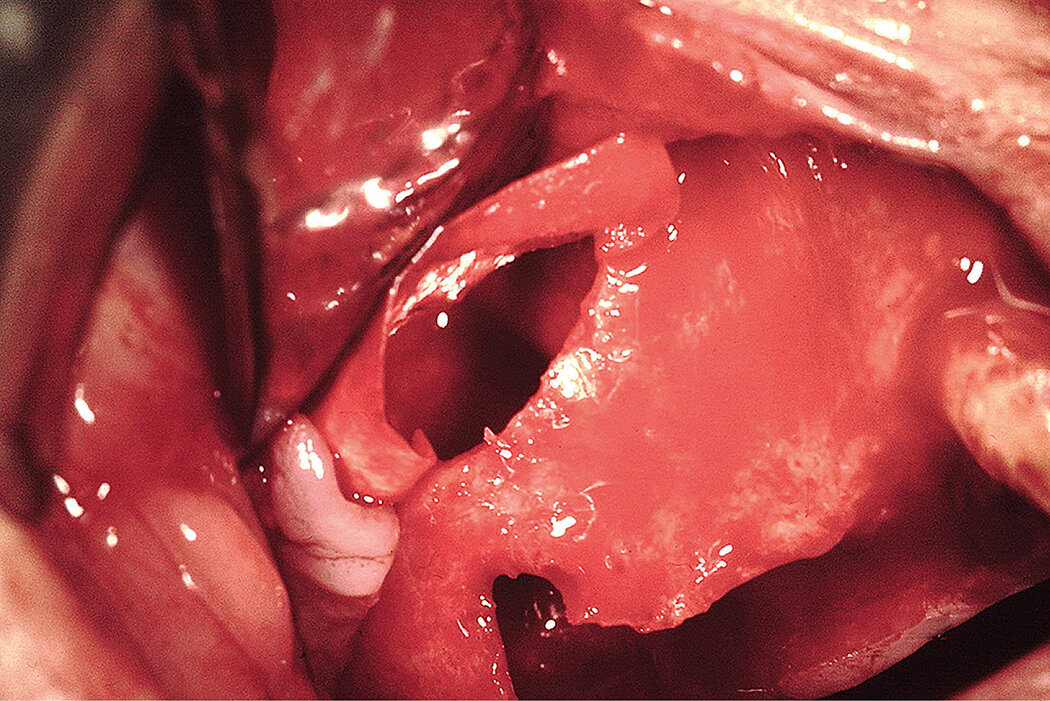

Prophylactic oral pre-medication of amoxicillin (1g) and dexamethasone (8mg) an hour before the procedure and a local application of 0.5% chlorhexidine for 2min. An incision was made on the alveolar crest and a vertical incision distal to the tuberosity was made to allow bone harvesting from this area to be mixed with the Geistlich Bio-Oss® . A window was cut through the lateral sinus wall cortex using a slow-speed round bone bur. At this point, the sinus membrane was carefully elevated from the sinus floor and medial sinus wall. Geistlich Bio-Gide® was used to repair the perforation. Since primary implant stability could not be attained, a delayed 2-stage implant placement was performed 5 months later. The maxillary sinus compartment was augmented with Geistlich Bio-Oss®. The fenestrated lateral wall of the maxillary sinus was covered with a Geistlich Bio-Gide® and the mucoperiosteal flap repositioned and sutured with a 3/0 Vicryl.